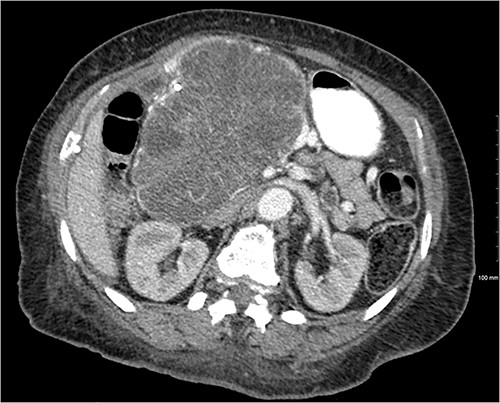

Patient presented one month later to the hospital from preadmission testing due to abnormal renal function. The patient endorsed dark urine, persistent unintentional weight loss, and decreased appetite with subsequent improvement of jaundice since PTC placement. She presented with abnormal serum biochemistry results: creatinine, 11.90 mg/dL [previously, 1.8 mg/dL] (normal range, 0.7–1.3 mg/dL); potassium, 2.9 mEq/L (normal range, 3.5–5.0 mEq/L); alkaline phosphatase, 142 U/L (normal range, 36–92 U/L); total bilirubin, 2.7 mg/dL (normal range, 0.3–1.2 mg/dL); direct bilirubin, 2.1 mg/dL (normal range, 0–0.3 mg/dL); aspartate aminotransferase (AST), 68 U/L (normal range, 0–35 U/L); alanine aminotransferase (ALT), 135 U/L (normal range, 0–35 U/L). Patient’s cancer antigen 19–9 was 2.2 U/mL (normal range, 0–37 U/mL). Abdominal ultrasonography showed a 13.0 × 9.4 × 8.3 cm mass in the right upper quadrant with numerous microcysts (Fig. 1).

Another abdominal CT was performed redemonstrating the large heterogenous mixed attenuating mass within the right abdomen measuring 14.0 × 10.0 × 13.0 cm likely originating from the pancreatic head with resultant displacement of the PTC anteriorly and to the right with extensive pancreatic ductal dilation (Figs 2 and 3).

Coronal CT showing a large heterogeneous mass in the pancreatic head with typical honeycomb feature.

Mass effect to abdominal viscera from the 14 × 10 × 13 cm pancreatic head mass.

The mass extended up into the base of the liver, effaced the portal and superior mesenteric veins (SMV) (Fig. 4), and displaced the hepatic and superior mesenteric arteries.